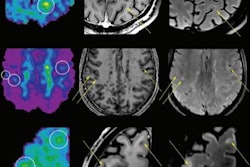

At the Mayo Clinic, Welker and colleagues have found that 7-tesla MRI is particularly helpful for assessing epilepsy because it demonstrates focal cortical dysplasia that can be missed on lower field strengths. It also shows promise for diagnosing mesial temporal sclerosis, another epilepsy-related condition; cavernous malformations; cerebellar hemorrhage; pituitary disease; and multiple sclerosis, as well as being used for presurgical mapping with functional MRI.

The advantages of 7-tesla MRI include increased signal-to-noise ratio -- more than double the ratio of a 3-tesla scanner -- higher spatial resolution (0.2 mm in plane), and improvements in contrast visibility. It also provides increased sensitivity to magnetic susceptibility (that is, how much a material will become magnetized in a magnetic field), which is especially helpful for susceptibility-weighted imaging and functional MRI.